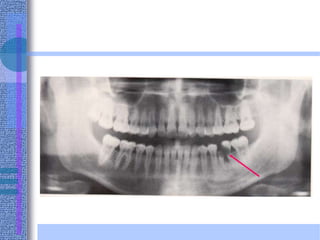

Indications:

1. Overall view of the teeth and facial bones.

2. Assessment of the presence and the position of multiple unerupted

or impacted teeth.

3. Assessment of gross pathological lesions as cysts or tumours.

4. Radiography of both rami, condyles and coronoid processes and

assessment of any TMJ abnormalities.

5. It reveals fractures of the mandible from the midline to the neck of

the condyle.

6. It reveals the maxillary sinuses, floor of orbits and nasal bone.

7. It demonstrates the presence and progress of any periodontal

disease in an overall way.

8. It is valuable in orthodontics as it reveals the unerupted or absent

teeth and relation of mandible to maxilla.

9. Assessment of degree of alveolar bone and relationship of the

teeth to mental foramen, inferior dental canal and alveolar margin

before implantology.